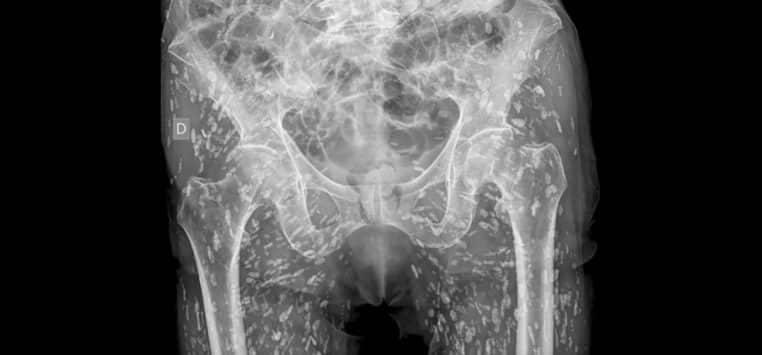

Si vous aimez manger votre steak saignant, ne faites pas la même chose avec de la viande de porc. Sur X, un médecin a partagé une vidéo qui montre les conséquences d’une viande de porc mal cuite. Et cela peut être dangereux. Sur son compte X, Sam Ghali publie une radiographie d’un homme infesté d’œufs de ténia.

Selon Sam Ghali, les œufs de ténia, ou kystes, peuvent se déplacer dans tout le corps humain. Pour le patient, ils étaient présents au niveau des hanches et des cuisses. Mais s’il n’avait pas fait une chute l’invitant à passer une radio, cela aurait pu avoir de plus lourdes conséquences. En effet, le patient aurait pu mourir…